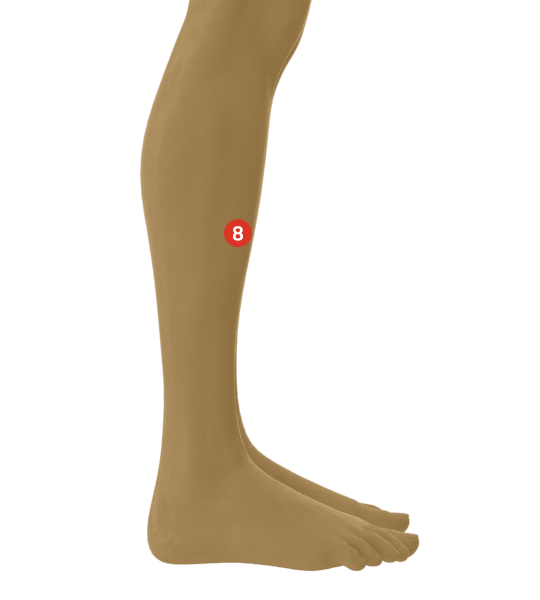

Επέλεξες την περιοχή, Πόνος στην κνήμη (Καλάμι)!

Οι πλήρως τεταμένοι μύες της κνήμης προκαλούν πόνο σε πολλούς ανθρώπους από το γόνατο έως το άκρο ποδός.

Γενικές πληροφορίες για το σημείο πόνου: Πόνος στην κνήμη (Καλάμι)